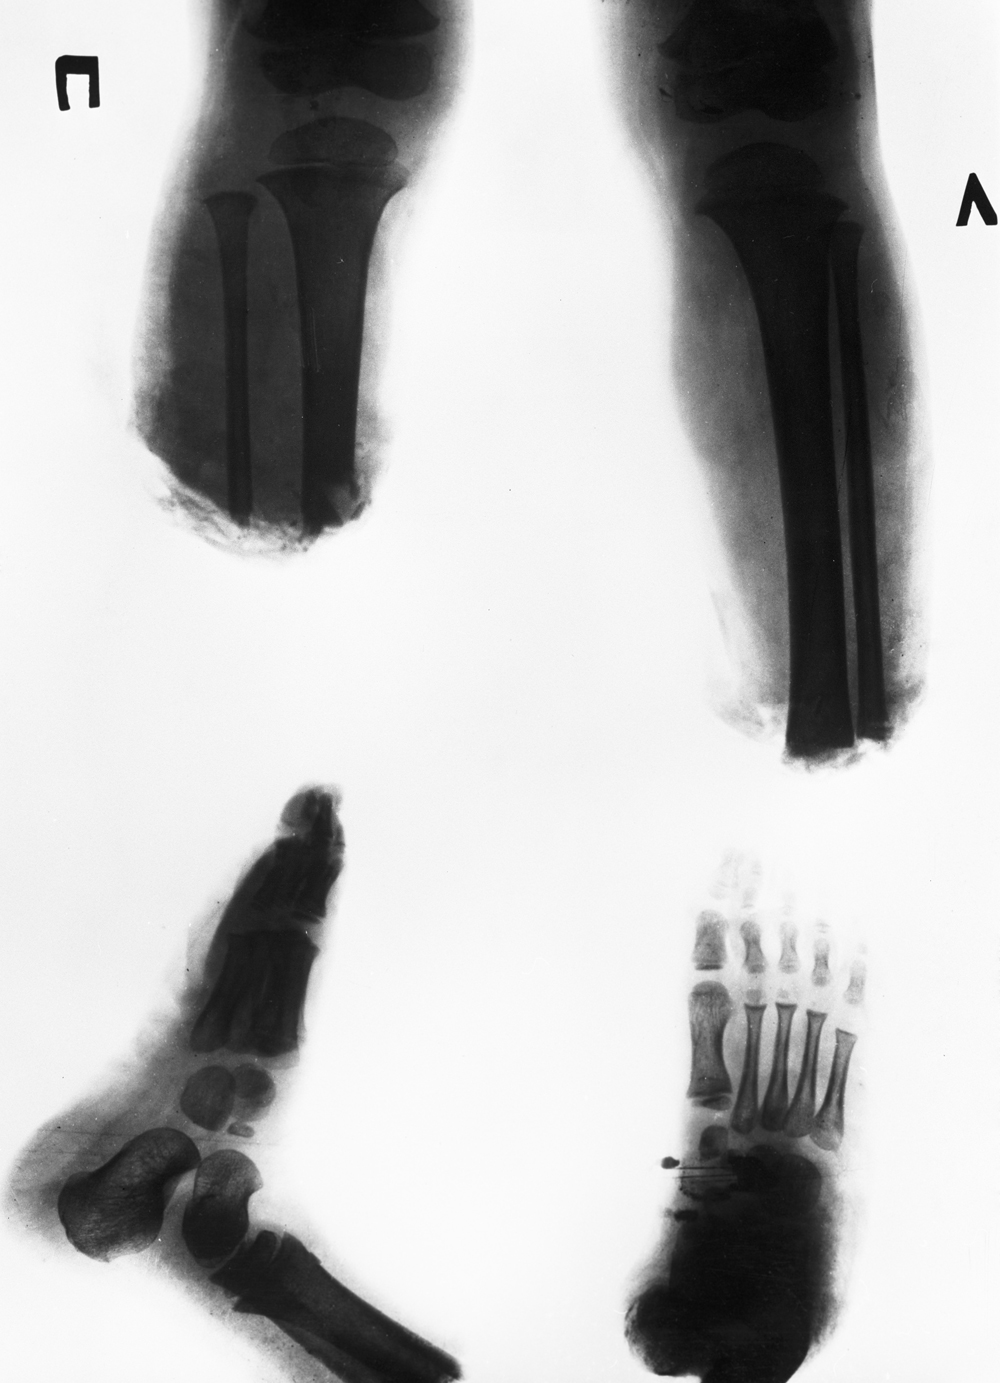

Рентгеновский снимок ног 3-летней литовской девочки Расы Прасцявичуте до операции по реплантации обеих стоп ног. Фото: РИА Новости/ Христофоров

Небо расчистили для Ту-134, в котором летела Раса и её ножки, обложенные мороженой селёдкой («Переморозили!» – будет потом чертыхаться хирург). На операционном столе в Филатовской больнице Раса была через 12 часов.

Раса Прасцявичуте после успешной операции по реплантации обеих стоп ног. Ее оперировал микрохирург Рамаз Датиашвили (справа). Фото: РИА Новости/ Владимир Вяткин